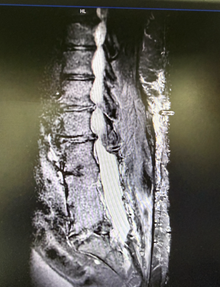

from clipboard

患者术前MRI

接诊后,疼痛科团队对患者进行了系统、全面的评估,结合其病史、临床表现及影像学检查结果,组织多学科会诊讨论。综合分析认为,该患者疼痛性质以神经病理性疼痛为主,且对常规保守及介入治疗反应有限。影像学评估提示,患者手术区域局部解剖结构明显异常,存在术后瘢痕粘连及椎管极度狭窄等改变,增加了电极置入的技术难度与操作风险。经多学科团队充分讨论与患者知情同意后,决定先行实施短时程脊髓电刺激作为疗效测试和安全性评估手段,再根据镇痛效果和耐受情况,审慎评估后续是否行永久性电刺激系统植入,并据此制定了周密、个体化的手术方案。